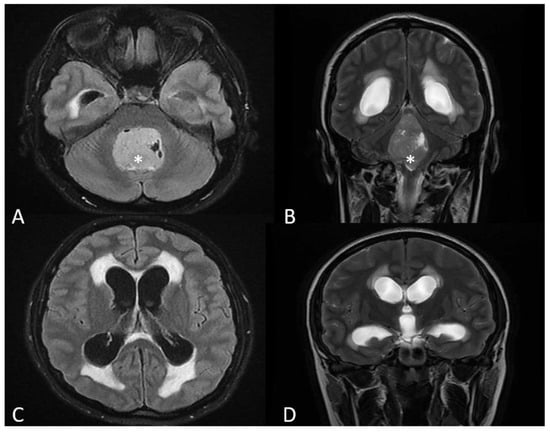

2. Case Presentation